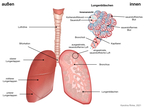

Lunge (Organ, Mensch)

(1024x768)